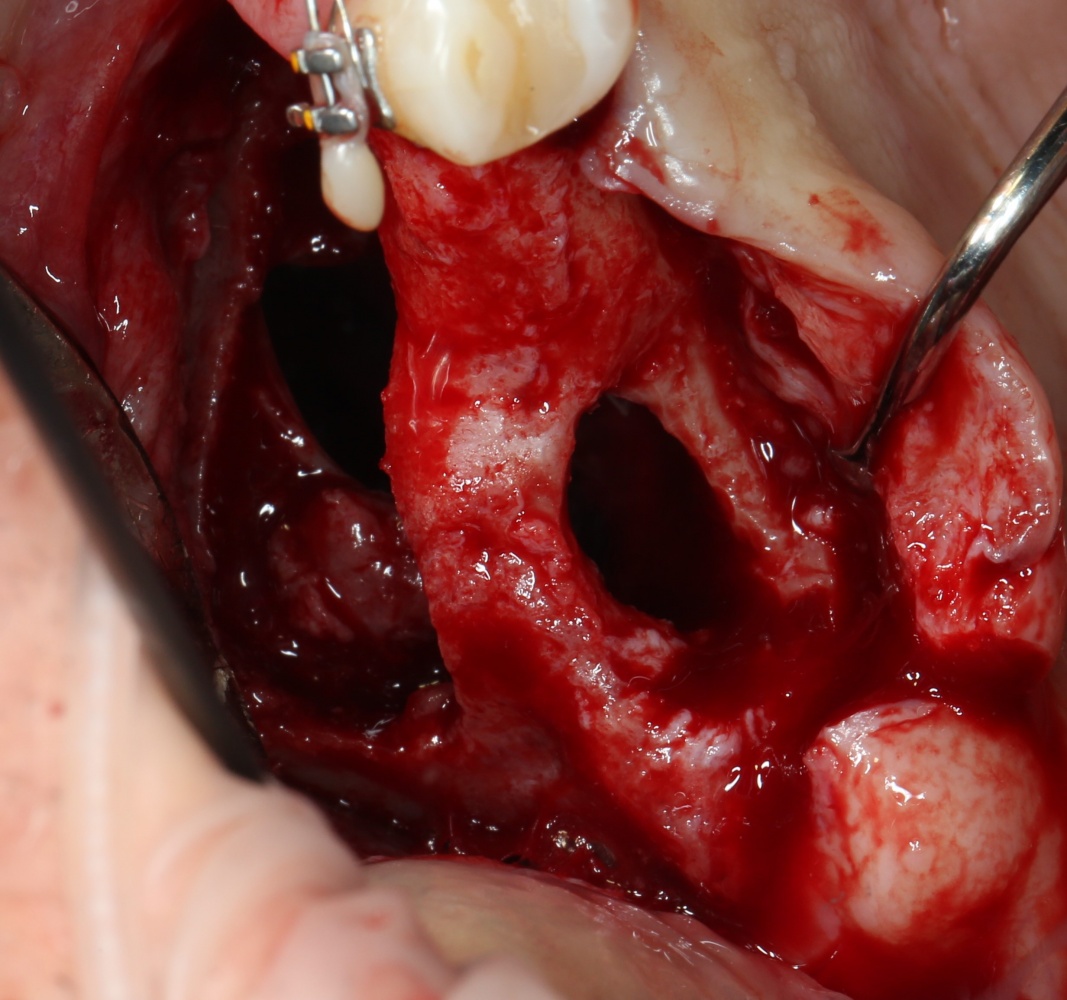

Как это делается, написано здесь>> и здесь>>, при этом существует ошибочное мнение, что большие апертуры доступа в верхнечелюстную полость тяжело заживают и оставляют дефекты кости. Покажу вам пример такого заживления.

Как видите. восстанавливается всё очень легко, никаких дефектов не остаётся, но при этом мы получаем важное преимущество: достаточную свободу движений при формировании субантральной полости и хороший визуальный контроль за состоянием слизистой оболочки. Никакая нажопная оптика или суперпупермикроскоп, к сожалению, не обеспечат подобный контроль при закрытом синуслифтинге. Да, операция получается травматичнее и масштабнее, чем «закрытый» синуслифтинг, но несёт в себе гораздо меньше рисков.